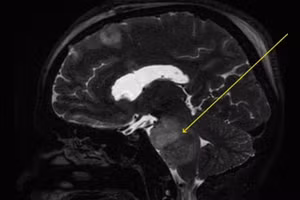

GD&TĐ - Khối u phát triển âm thầm trong nhiều năm, gây chèn ép nhiều cấu trúc quan trọng trong não.